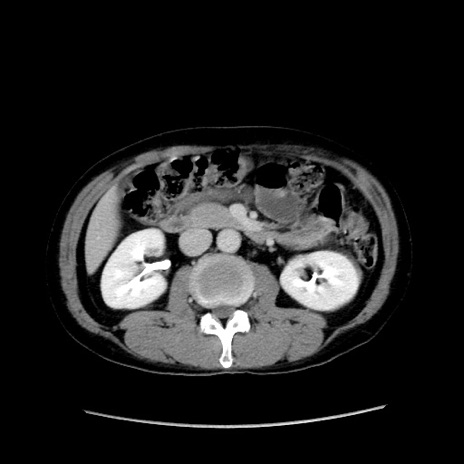

症例37(横断像)

【症例】40歳代 男性

【主訴】腹痛

【現病歴】4時間ほど前に電車に乗車中に臍部上より腹痛出現。徐々に増悪し起立困難となり、救急外来受診。生ものは数日食べていない。今朝お雑煮を食べた。

【身体所見】BT 36.8℃、BP 117/84mmHg、HR 91/min、SpO2 97%、苦悶様、腹部:臍上部広範囲圧痛あり、反跳痛±

【データ】WBC 8100、CRP 0.03